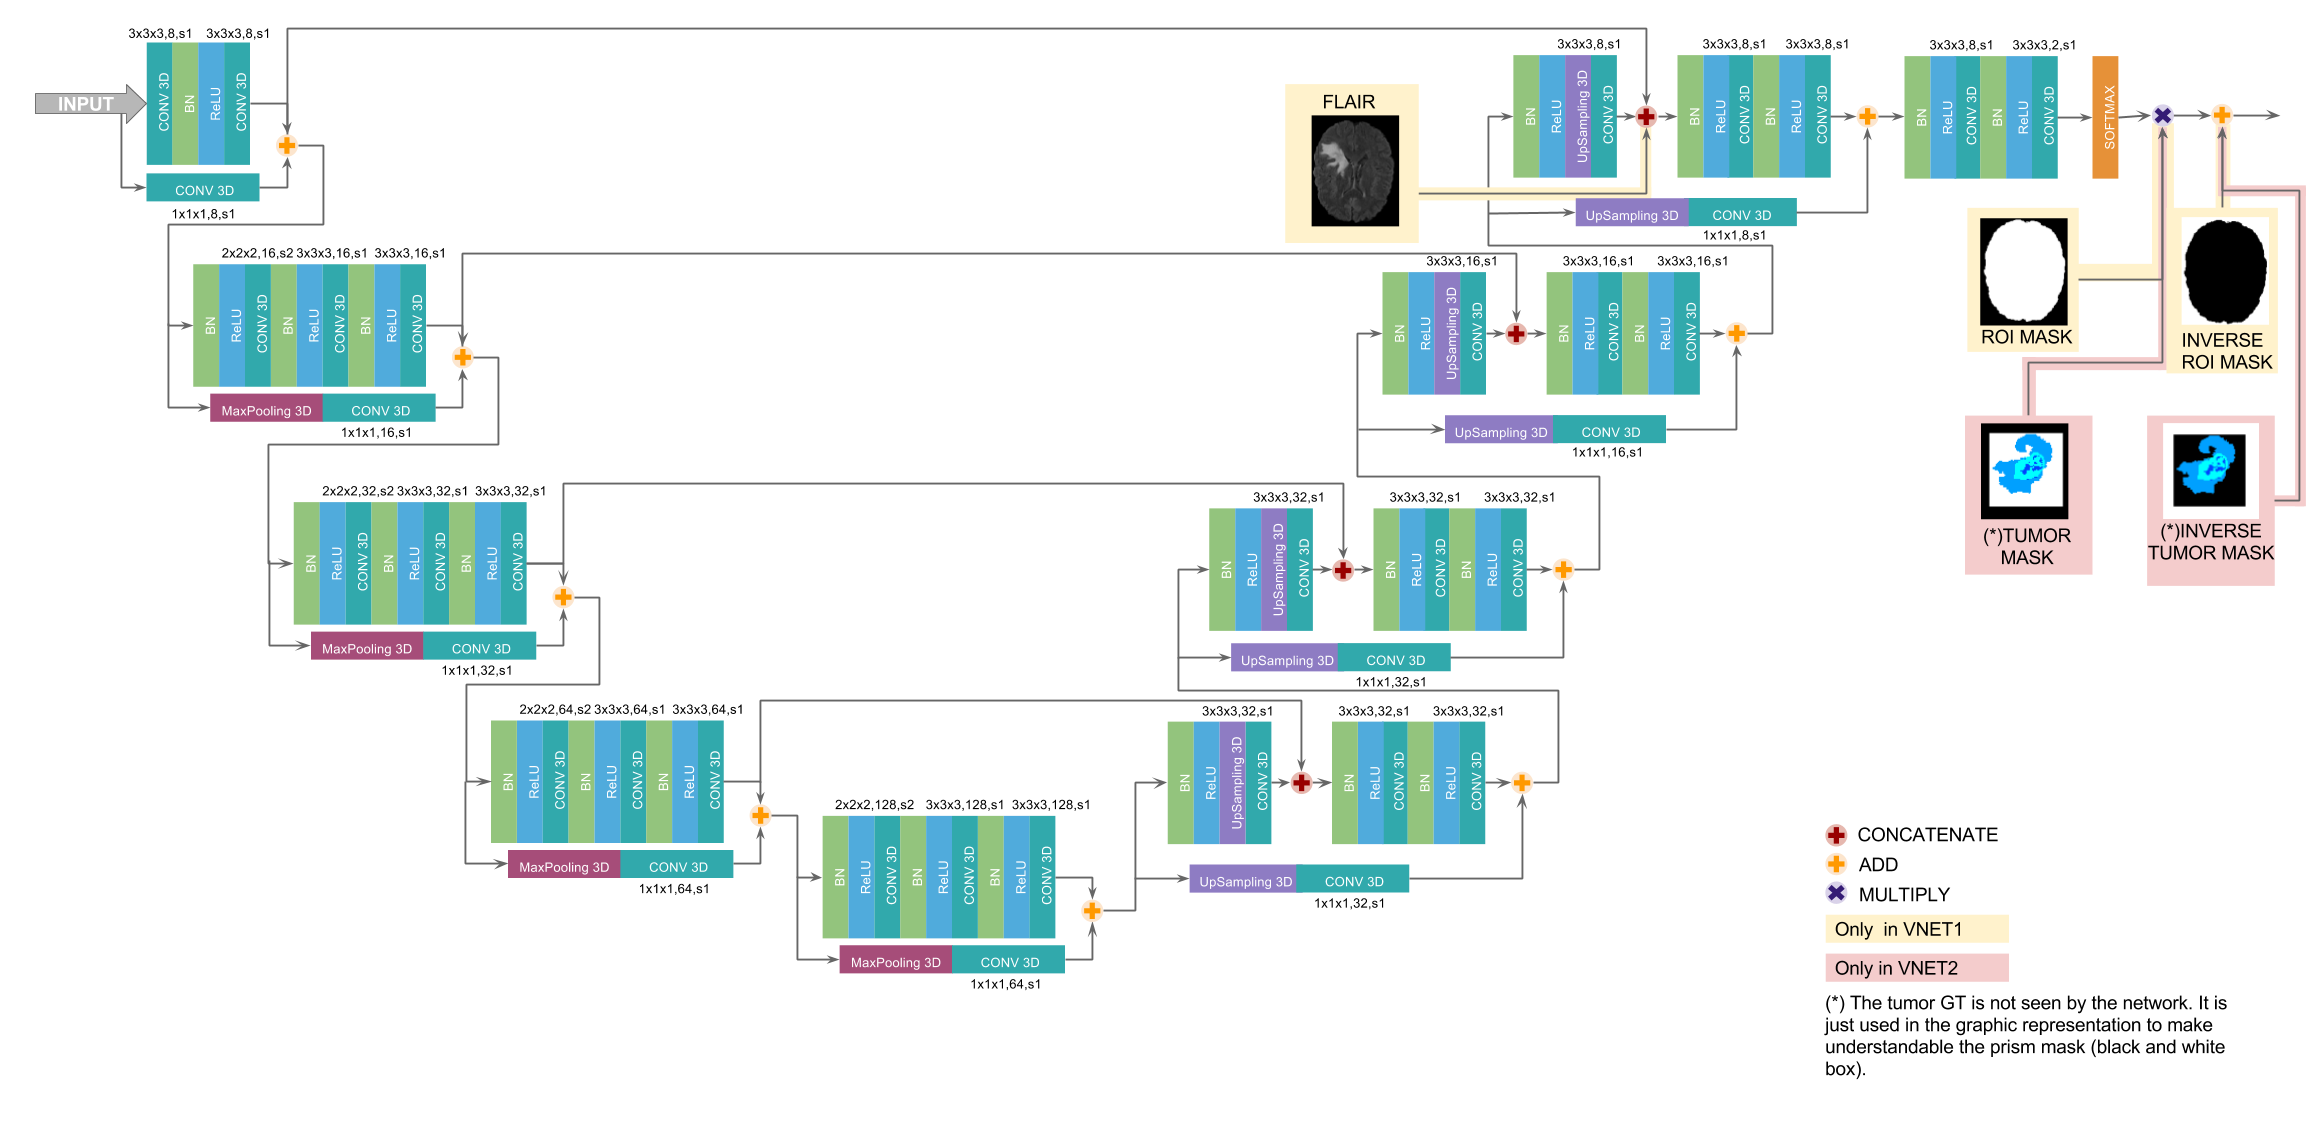

Our network is a variant of V-Net [13] that aims at reducing the overall number of parameters by using smaller filter sizes (3x3x3 instead of 5x5x5) and changing the non-linearity from PReLU to ReLU. In addition, we use batch normalization before the non-linearity to account for internal covariate shift. Based on insights from [18], we also reformulate the short residual connections in order to improve gradients flow across the network by using identity mappings as residual connections. In the case of dimensions mismatch in the addition layer, we minimally modify the residual connection with max-pooling and repeated up-sampling for spatial correspondence and 1x1x1 convolutions to match the number of channels. For better understanding, we show in Fig. 2 the main changes from the original V-Net.

We use ROI masks before the final predictions both during training and inference in order to smooth the class imbalance problem, specially for small sub-tumor regions. The ROI mask forces the outer voxels to belong to the background class with full probability by first multiplying them by 0 and turn their probability of belonging to the background class to 1. The multiplication prevents the backpropagated signal from going through the outer voxels and thus, it does not contribute in the learning process. The overall architecture is shown in Fig. 3.

Each network in the pipeline performs a different task and thus, they can be independently trained. Instead of using patch-wise training and non-uniform sampling strategies to account for class imbalance, we use dense-training with a single subject per batch. The first network is trained as a binary segmentation problem with tumor/non-tumor classes and outputs a raw segmentation of the whole-tumor region. It takes the four modalities (T1, T1c, T2 and FLAIR) as inputs and uses the FLAIR intensity information in the deeper layers of the network by concatenating it with the predicted feature maps from the last level in the expanding path of the network. The network makes use of a brain mask in order to consider only brain tissue voxels for training. The loss function used is the modified dice coefficient (1) suited for binary segmentation tasks with imbalanced data:

The second network is trained as a multi-class segmentation problem with four classes (non-tumor, edema, enhancing core and non-enhancing core). It also uses the four MRI modalities as input. From the ground-truth labels, we generate a rectangular mask that covers the whole tumor and it is used to train the network only in the vicinity of the tumor, avoiding to train on brain tissue far from the tumor region. As we use dense-training with a single subject per batch, the use of raw tumor masks in the training procedure helps to reduce the high class imbalance present among different classes. The loss function in the second network is a combination of cross entropy () and the dice coefficient for each tumor sub-region (whole tumor (), enhancing tumor () and tumor core ()). We empirically choose the values for the weights in both parts of the function: